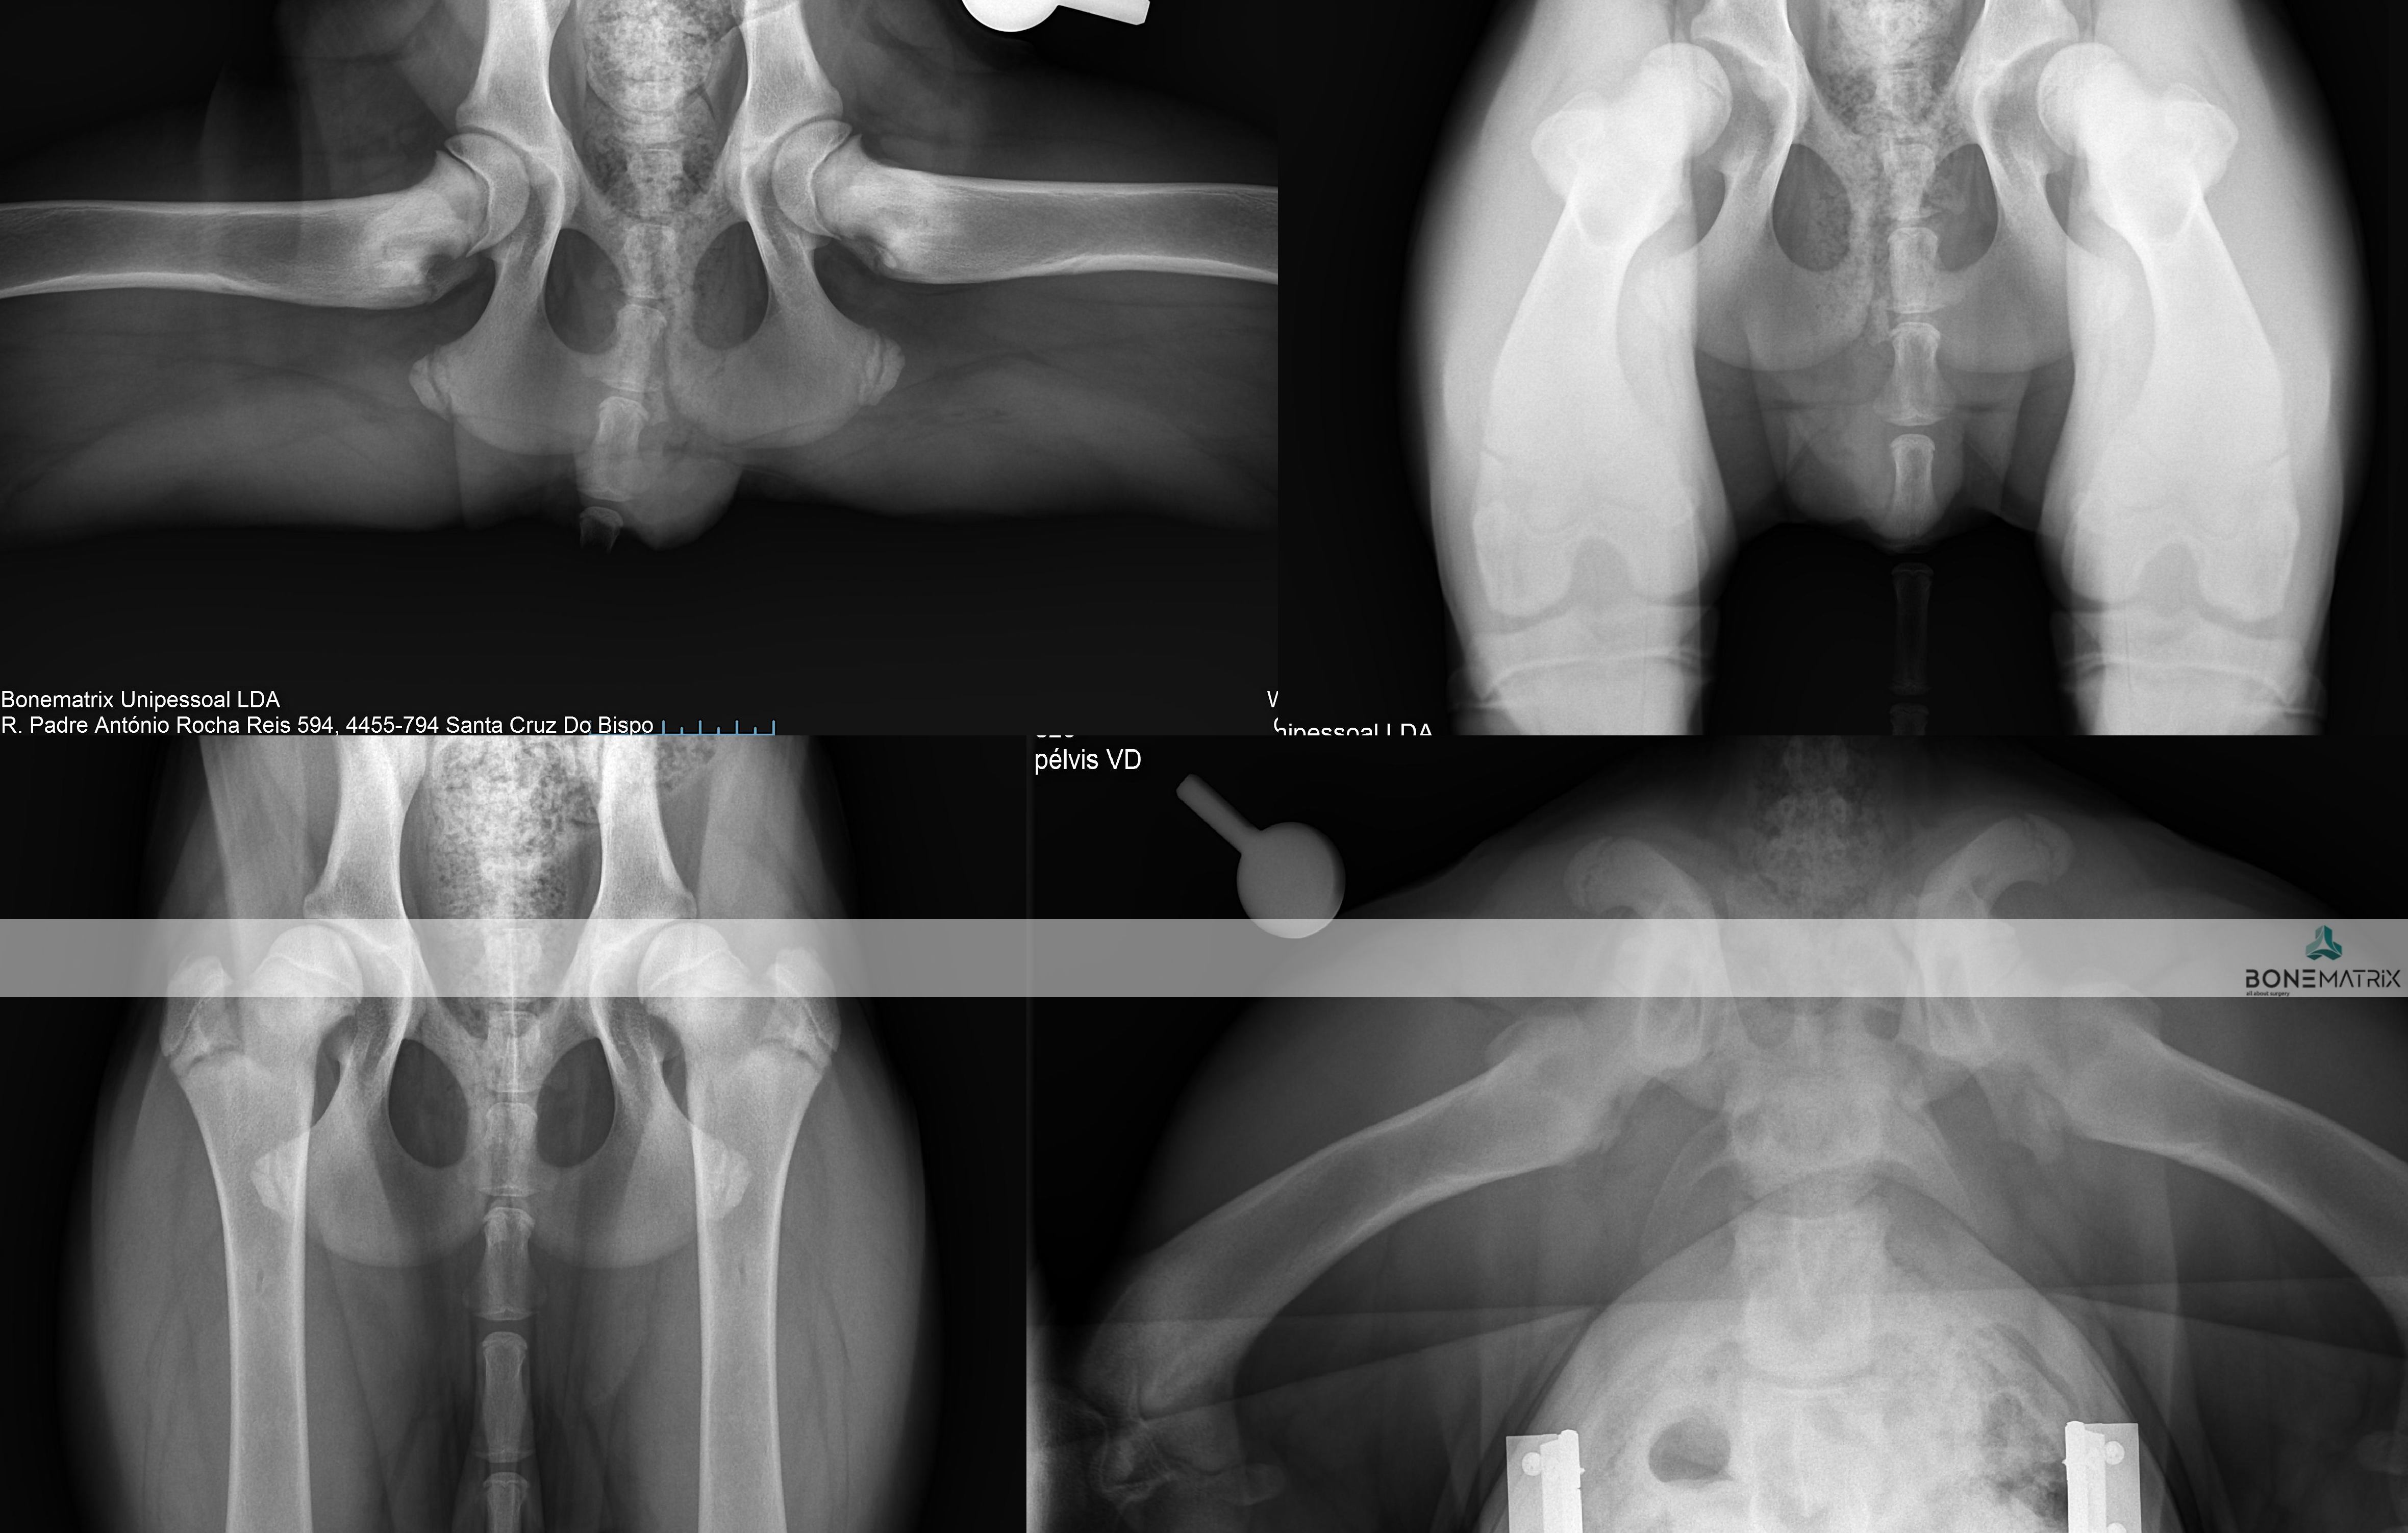

O que é?

A displasia de anca é uma patologia de desenvolvimento expressa na articulação coxo-femoral (entre o fémur e a pélvis). Esta é a doença ortopédica mais comum nos cães.

A sua origem é maioritariamente genética, podendo por vezes apresentar também uma influencia ambiental.

Como se desenvolve a doença de displasia de anca?

Inicialmente existe uma laxitude dos tecidos moles (capsula articular e musculatura envolvente) que permite juntamente com uma má cobertura da cabeça femoral pela componente óssea da pélvis (acetábulo). Estes fatores em conjunto levam à possibilidade de um movimento excessivo entre os componentes desta articulação, o que faz com que seja possível luxar cabeça femoral.

Esta luxação ocorrendo repetidamente leva ao desenvolvimento de alterações ósseas de ambas as componentes articulares que contribuem para a exacerbação da capacidade de luxação. Entrando assim num ciclo a capacidade de luxação leva a alterações articulares que permitem cada vez mais a luxação da articulação.

Esta movimentação dentro da articulação eventualmente leva ao desenvolvimento de um quadro de osteoartrite que conforme a severidade da doença se poderá apresentar também este com uma severidade correspondente.

Qualquer raça pode apresentar displasia de anca, contudo algumas são mais predispostas, nomeadamente as raças de porte grande a gigante, como Pastor Alemão, Newfoundland, raças Retriever e Rottweiller.

O diagnóstico de displasia de anca deve ser realizado idealmente antes dos 5 meses, daí a importância do despiste precoce da doença.

Uma vez que este seja detetado cedo na vida do animal poderão ser consideradas opções de tratamento preventivo. Na maioria destes casos os animais apenas apresentam laxitude articular, sendo com frequência assintomáticos clinicamente. Por este motivo a intervenção cirúrgica nestas idades impede que um animal que iria desenvolver a doença a desenvolva efetivamente ou então que desenvolva apenas um quadro de osteoartrite muito ligeiro, que possa ser gerido medicamente numa idade geriátrica.

O diagnóstico é feito com recurso a um estudo radiográfico de despiste de displasia de anca (este estudo pode ser realizado a partir dos 4 meses).

Com o decorrer da doença os animais podem apresentar sintomatologia associada que nos leva à suspeita do diagnostico, nomeadamente, claudicação, incapacidade de fazer determinados movimentos, incapacidade de realizar saltos, início de marcha "à coelho", dor articular, teste de Ortolani e Barden positivos (avaliações especificas de exame ortopédico direcionadas para esta doença).

O tratamento indicado depende da idade do paciente e das características estudadas da articulação.

Quando a idade do paciente o permite e este se revela um bom candidato, pode em idade imatura, ser realizada uma DPO (double pelvic osteotomy), sendo este um procedimento preventivo do desenvolvimento de displasia de anca.

Quando o animal é adulto a única opção de tratamento curativa passa pela prótese total de anca (THR). Esta permite substituir a articulação afetada na sua totalidade e devolver a qualidade de vida ao paciente até ao fim da vida dele.

DPO (double pelvic osteotomy) é um procedimento preventivo realizado em pacientes onde o despiste de displasia de anca prevê o desenvolvimento desta doença.

Inicialmente deve ser realizado um despiste de displasia de anca com recurso a um estudo radiográfico especifico para que o paciente seja avaliado e seja definido como um bom candidato à aplicação desta técnica.

A DPO consiste na realização de dois cortes ao nível da pélvis que permitem a rotação do fragmento criado. Este fragmento inclui a porção articular da pélvis, na articulação coxofemoral (o acetábulo).

Ao rodar este fragmento conseguimos uma maior cobertura da cabeça femoral pelo acetábulo, impedindo o movimento de saída da cabeça femoral de dentro do acetábulo. Ao impedir este movimento (laxitude articular) impedimos o desenvolvimento de lesões de osteoartrite provocada por ele, e desta forma impedimos o desenvolvimento da doença de displasia de anca.

Após rotação do fragmento, este é estabilizado na posição pretendida com recurso a placas bloqueadas especializadas para a realização desta cirurgia, garantindo assim a cicatrização do osso no ângulo previamente definido.

Este procedimento deve ser realizado idealmente aos 5.5 meses daí aí importância dos despiste de displasia de anca serem realizados muito cedo na vida do animal.

Os pontos essenciais que definem um bom candidato são a idade do paciente, desenvolvimento mínimo de osteoartrite a nível articular e presença de um sinal de Ortolani positivo (teste realizado durante a consulta pré-despiste).